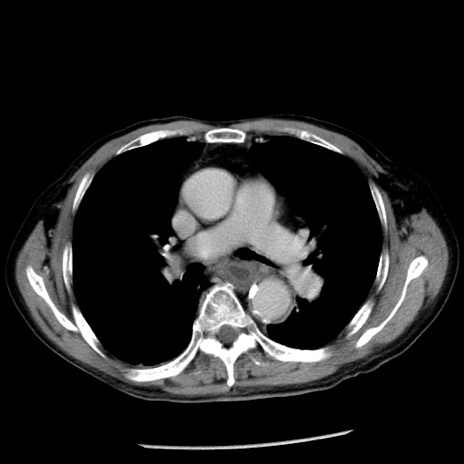

症例26(横断像)

【症例】80歳代男性

【主訴】嘔吐

【現病歴】昨晩2回嘔吐あり、今朝になっても嘔吐あり。来院。

【既往歴】胃潰瘍

【身体所見】意識清明、BT 37.6℃、BP 166/95mmHg、HR 100bpm、SpO2 97%、腹部:平坦・軟、腸蠕動音聴取良好、圧痛なし。

【データ】WBC 21900、CRP 1.46